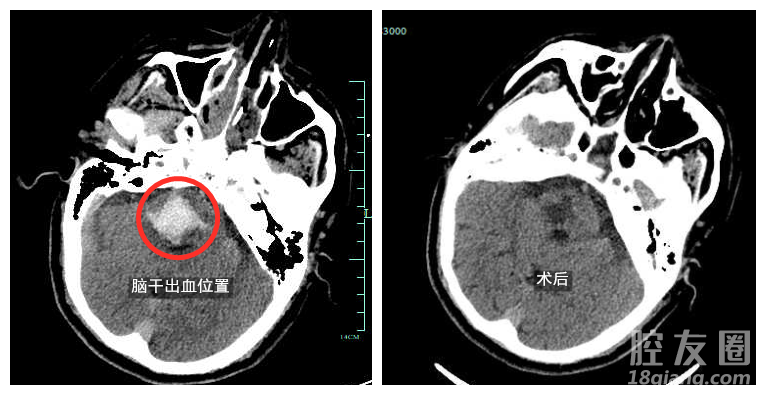

急诊医生评估发现姜大爷格拉斯哥评分只有5分(针对昏迷程度的判定,正常人为15分,最低3分),双侧瞳孔缩小,对光反射消失。同时出现呼吸困难,血氧饱和度下降,生命垂危。颅脑CT检查显示:患者脑干出血,出血量大约12ml。

生死营救,危在旦夕,浙大四院医护团队尽全力抢救,应用手术机器人辅助开展手术手术过程很顺利,在神经外科陈毅力主任的指导下,王铂和徐丹医生通过机器人的引导,将一根细细的引流管置入了血肿腔的中心,术中轻柔地吸出大部分血肿,术后复查CT发现,脑干内血肿已经彻底清除。